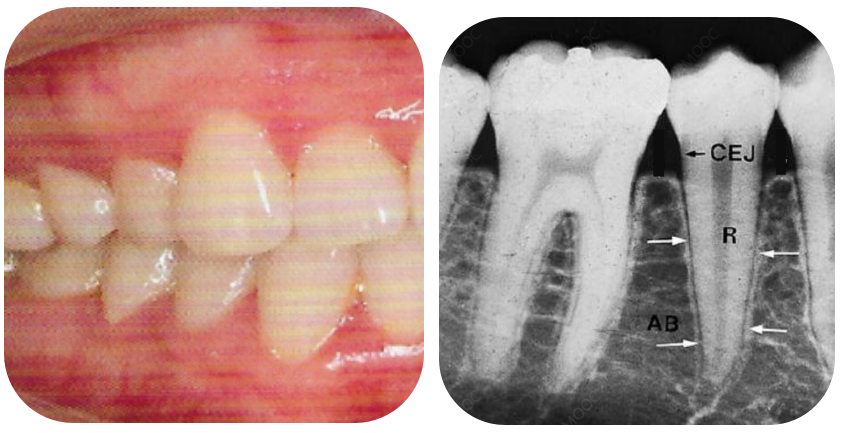

健康牙龈:牙龈颜色粉红,不易出血,牙槽骨高度正常,但仍需定期洁治,预防牙周炎。

早期牙周炎:牙龈出血、口臭,易被误认为“上火”。此时牙槽骨轻度吸收,骨高度降低。可经过牙周基础治疗(洁治、龈下刮治等)控制炎症,及时止损。

中期牙周炎:牙龈萎缩、牙缝变大,常误以为是“自然衰老”。此时牙槽骨已明显吸收,但牙齿松动可能仍不明显。如牙周基础治疗效果一般,通常会建议牙周手术治疗。

晚期牙周炎:牙齿松动、移位。此时牙槽骨吸收严重,牙齿松动明显,牙周治疗为时已晚,不仅费用高,并且效果欠佳,严重的牙槽骨吸收还会影响后续镶牙或种牙的效果。